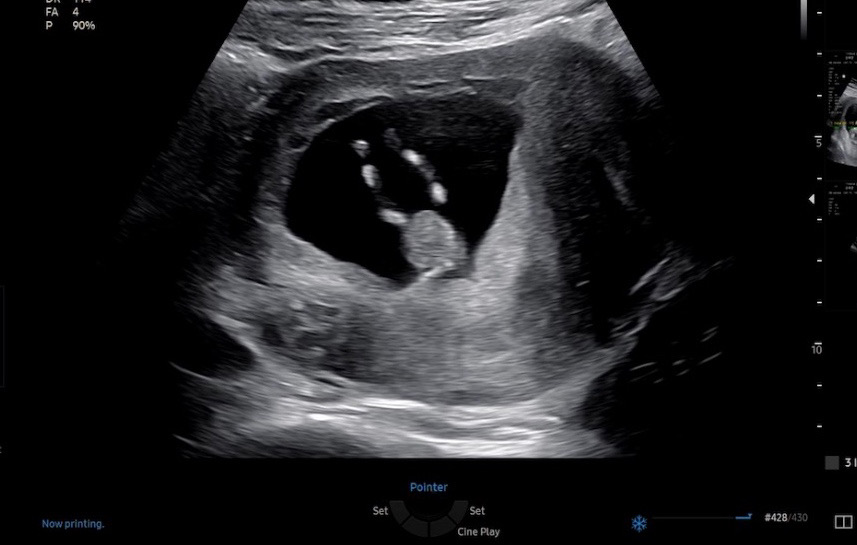

초음파 다리사이 같이 봐주세요 !! ㅎㅎ

아들들은 존재감이 뚜렷하던데! 어떠세요?! 혹시 저와 비슷했는데.. 이후에 미사일이 나오신 분들도 계신가요???🤣

몇주차 신지? 저는 13주 초음파에 흐릿하게 미사일보구 15주차에 아들이고 반전 없다하셨는데